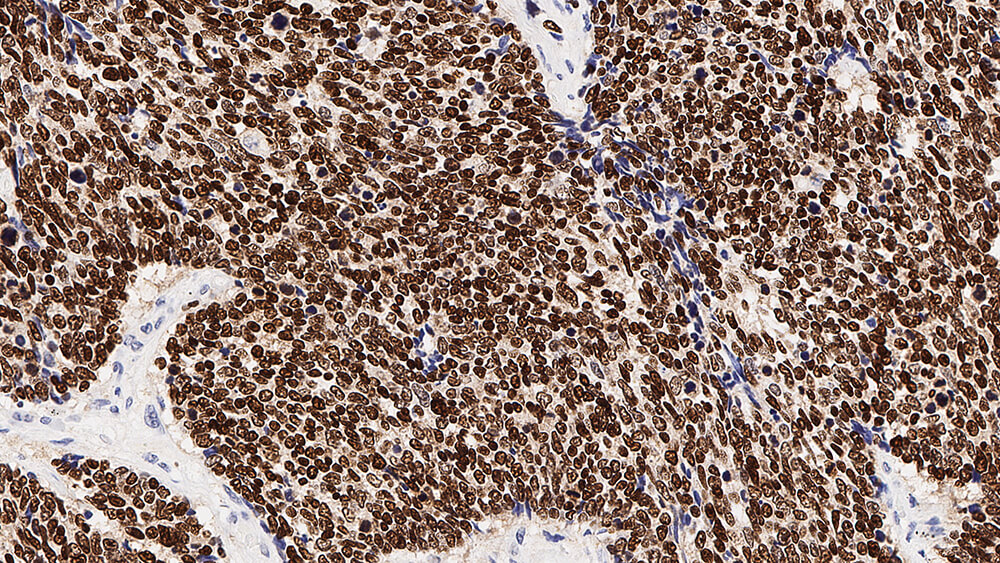

Human thyroid: immunohistochemical staining for Thyroid Transcription Factor-1. Note nuclear staining of thyroid epithelial cells. Thyroid Transcription Factor-1: clone SPT24

TTF-1 wird ebenfalls bei papillären, follikulären Karzinomen und beim Struma, einer nicht-bösartigen Schwellung der Schilddrüse exprimiert, jedoch nicht in anaplastischen Schilddrüsenkarzinomen.